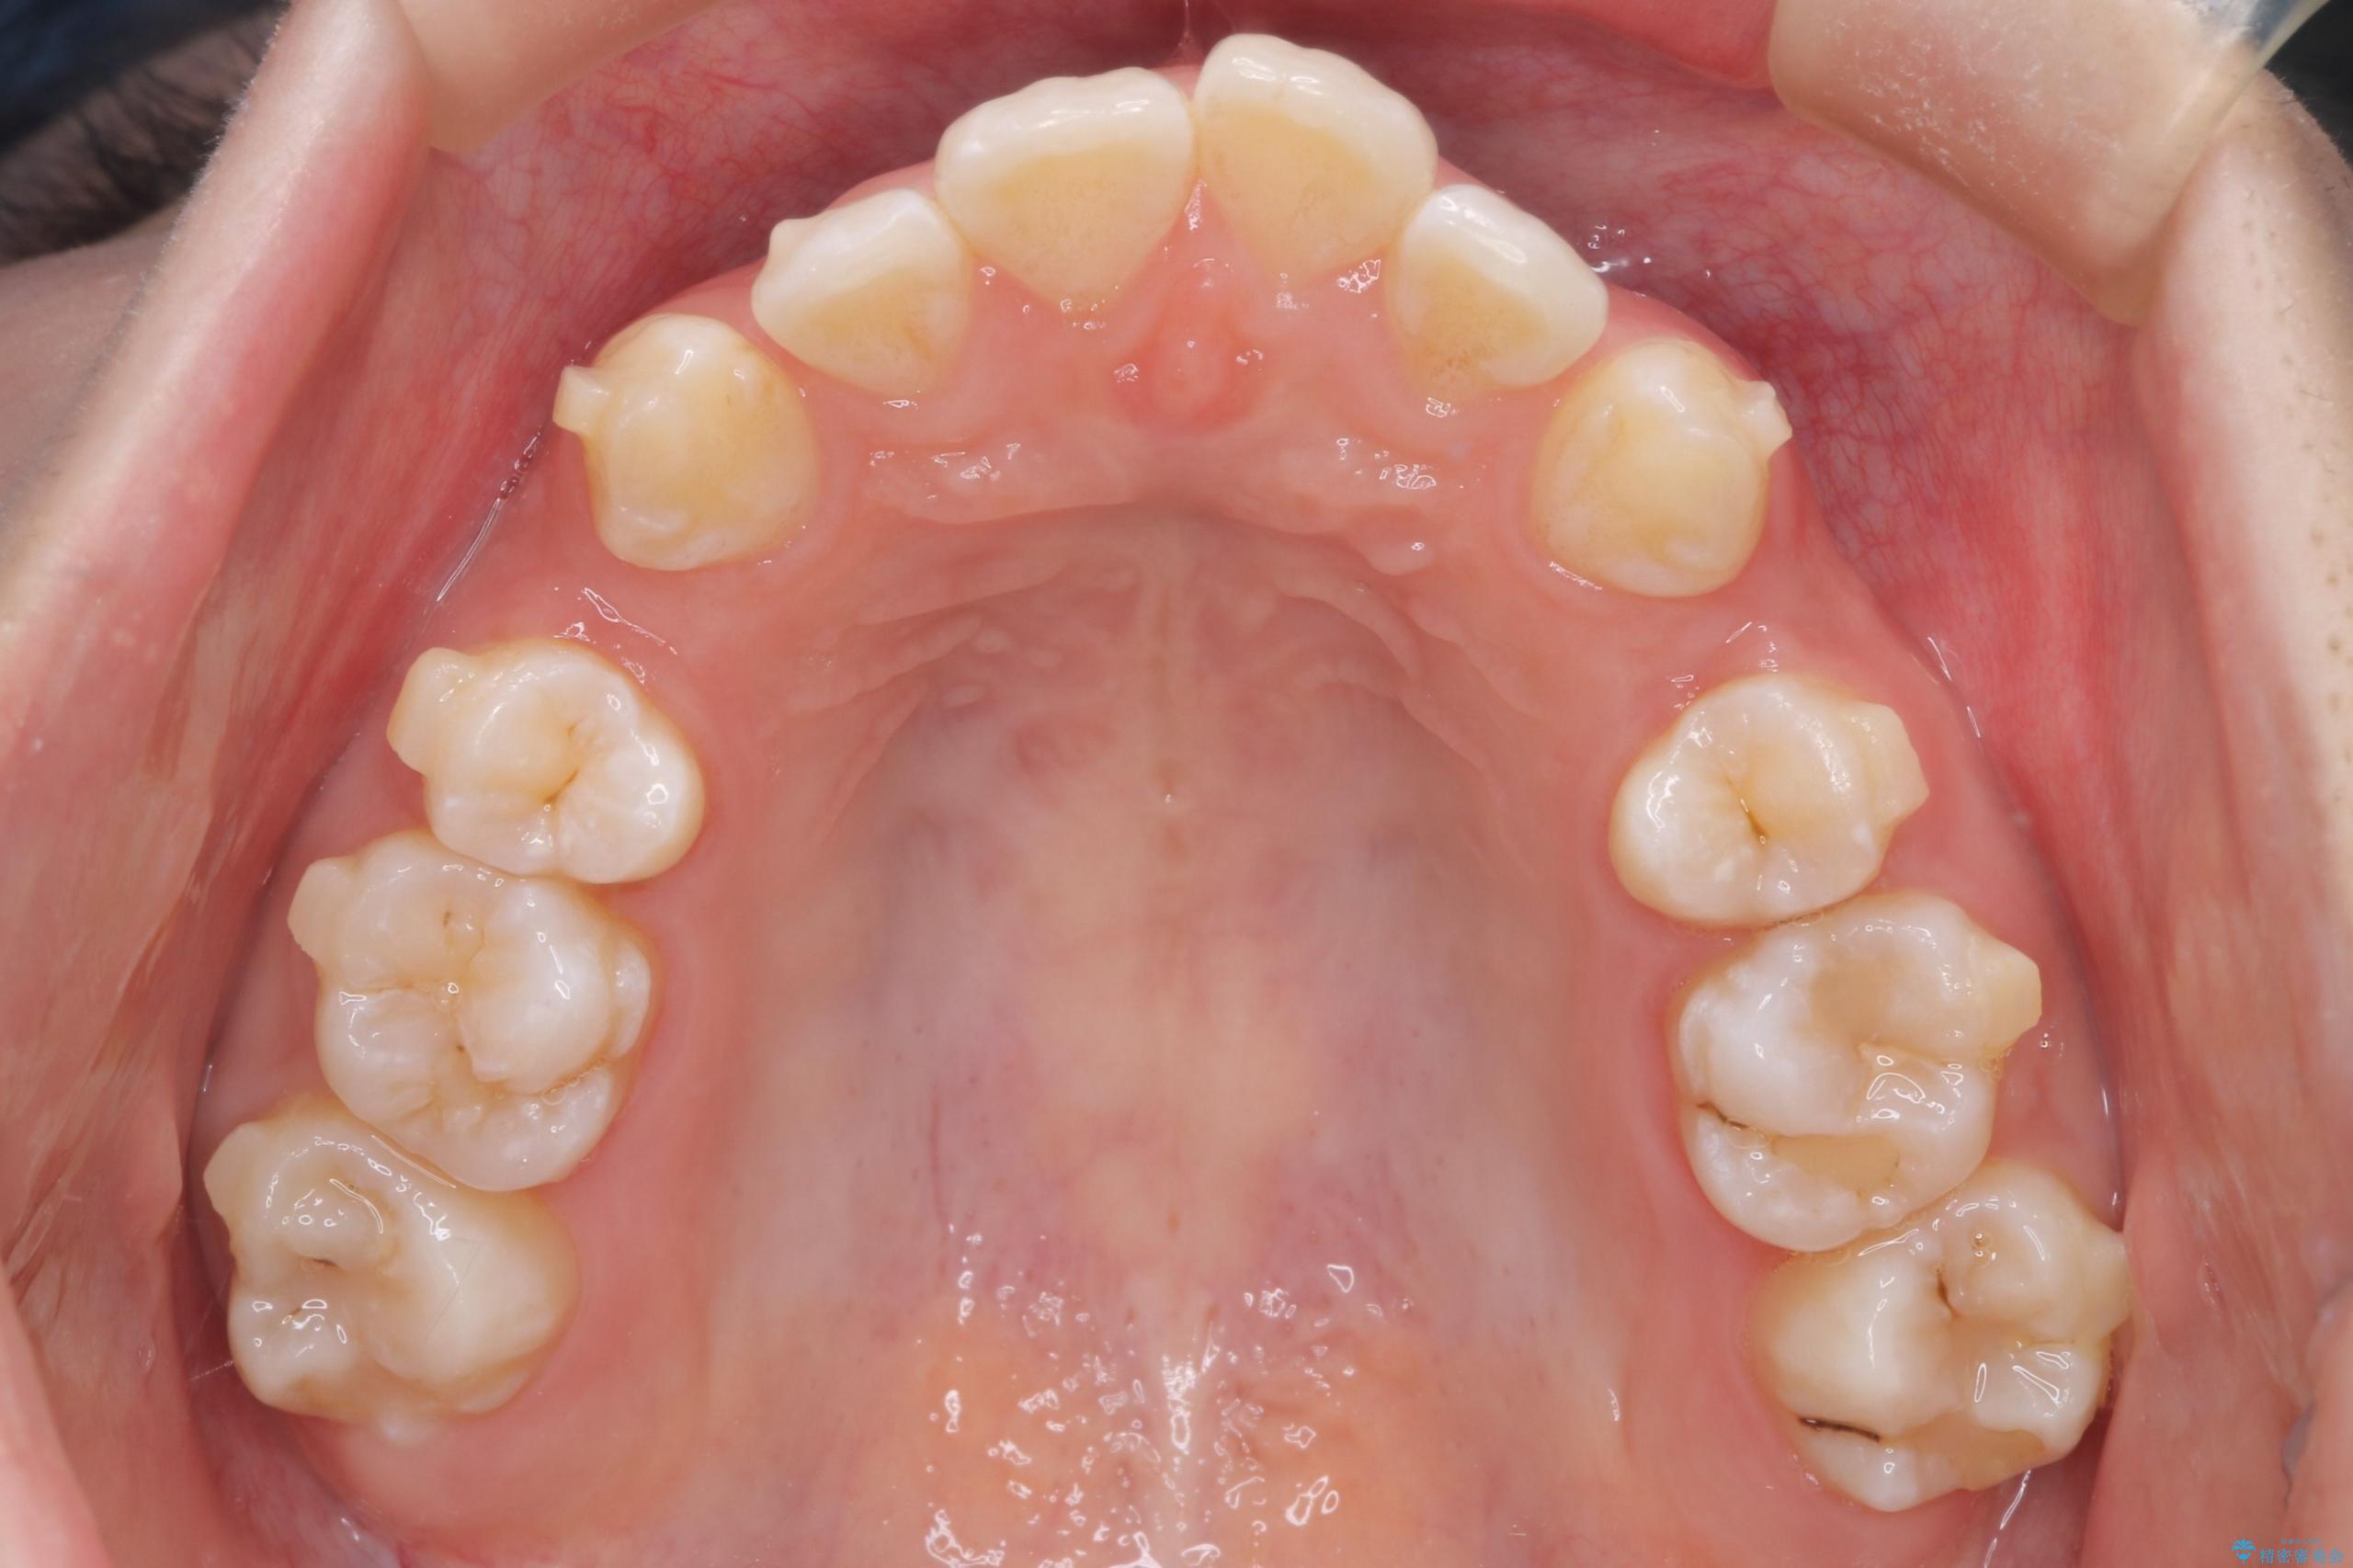

- 前歯から奥歯にかけて歯の重なりが激しい歯のがたつき(重度叢生)を主訴にご来院されました。精密検査の結果、歯が並ぶスペースが大幅に不足しており、歯並びを整え、口元を美しく引っ込めるためには、スペースの確保が必要と診断しました。そこで、上下左右の第一小臼歯(4番目の歯)を計4本抜歯し、そのスペースを利用して歯並び全体を整える抜歯矯正の治療計画を立案。装置には、透明で目立たないインビザラインを採用し、審美性と治療効果の両立を目指しました。

今回の治療では、重度の叢生を改善するため、まず計画通り上下左右4本の小臼歯を抜歯し、歯を並べるための十分なスペースを確保しました。装置には透明で取り外し可能なインビザラインを使用。抜歯によってできたスペースを最大限に活用し、マウスピースを定期的に交換しながら、デコボコを解消しつつ、前歯を効果的に後退させました。

治療の結果、長年の悩みであった重度の歯のがたつきが解消され、口元の突出感も改善。機能的にも安定し、審美的にも美しい、理想的な歯並びを獲得していただけました。